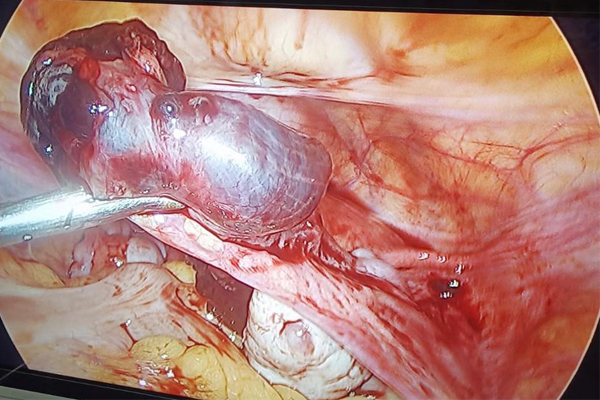

Dr. Mohankumar Veereshaiah has specialised in endoscopic surgeries in Gynaecology - (Laparoscopy and Hysteroscopy). He has an experience of 25 years. He has been giving excellent care to all his patients. His main location of practice is Navi Mumbai. He is attached to almost 30 hospitals in all over Navi Mumbai and all corporate hospitals like APOLLO, FORTIS, KOKILABEN, MGM Hospitals.

He has performed more than 15000/- surgeries to date. His vast experience in the field allows him to give top notch treatment to his patients. He has conducted many surgical conferences to teach his colleagues and students.